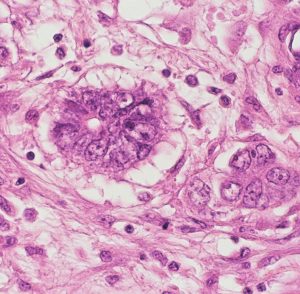

組織学的には,円柱様ないし楕円形の上皮様細胞の網状配列構造を示す腫瘍であり,一部にSchiller-Dubal bodyと呼ばれる血管周囲に集族する特徴的な細胞配列が見られます。これは,一層あるいは多層の上皮様細胞が,中心となる血管をやや離れて取り囲むように並ぶ構造です。また,PAS陽性の好酸性球状体が見られAFPが強陽性となります

視床下部に発生したchoriocarcinomaの病理像(左からHE染色, HCG染色, PLAP染色):腫瘍の大部分にHCG陽性細胞が認められますが,一部ではPLAP陽性のgerminoma細胞様の腫瘍細胞も散見されます。